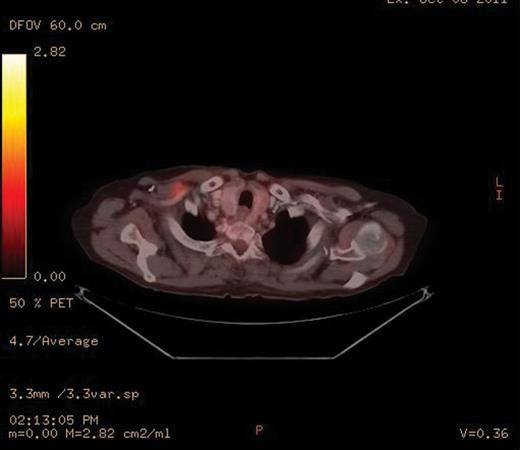

A PET-CT was performed, which demonstrated a round enhancing 1.8 × 1.5 cm right subpectoral lymph node with FDG uptake and a maximum SUV of 4.0 suspicious for metastatic disease (Figs 1 and 2). Additionally, an incidental 4.1 × 3.4 cm mass within the midpole of the left kidney was heterogeneously enhancing with increased FDG uptake and a maximum SUV of 8.6 suspicious for a renal cell carcinoma or less likely a transitional cell carcinoma (Figs 3 and 4).